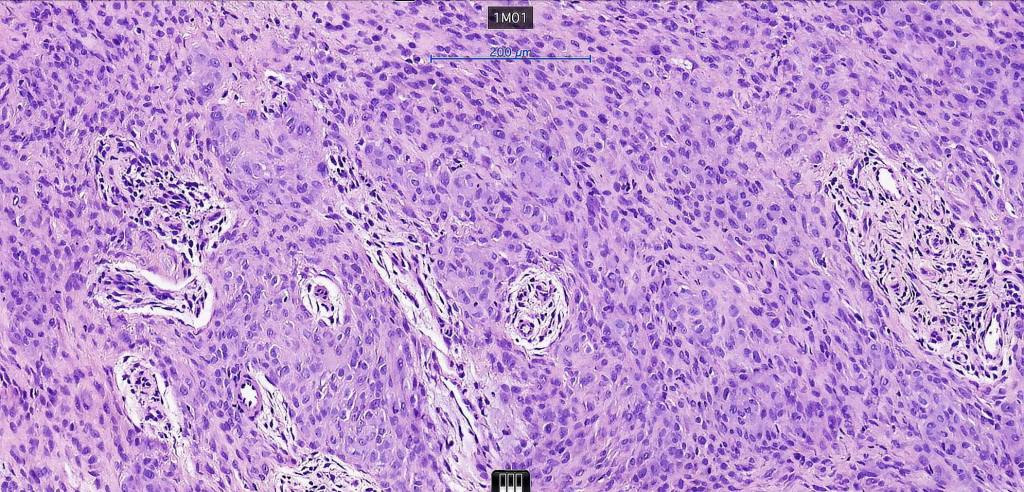

Histological features

•Pure population of myoepithelial cells dispersed in sheet-like, reticular, whorled or fascicular patterns in a myxoid or hyaline stroma

•Cell types include epithelioid, spindled, histiocytoid & plasmacytoid

•Syncytial myoepithelioma characterized by sheet-like growth of ovoid to spindle cells with pale cytoplasm, syncytial borders & vesicular nuclei